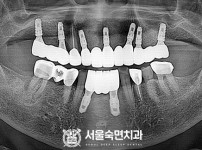

임플란트-전후사진4

치과를-선택할-때-꼭-확인하세요-서울숙면치과-임플란트-전후사진